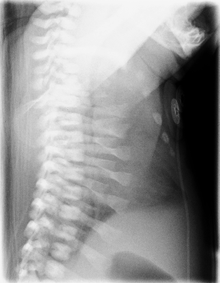

CXR of a newborn with asphyxiating thoracic dysplasia. Note the short ribs. | |